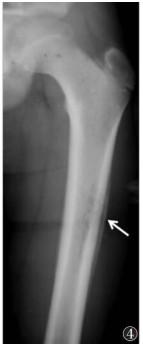

薄层骨膜反应通常提示为病变早期、病变进展较快及侵袭性较强[4]。轻度增厚的骨膜表面在短时间内仅有较少的钙盐沉积,多见于急性骨髓炎早期(图 4)、疲劳骨折的早期、尤因肉瘤(图 5)、骨肉瘤等。厚骨膜反应通常提示病变进展缓慢[5]、病程较长。骨膜增厚较明显且有较多的钙盐沉积,多见于良性病变,如慢性骨髓炎(图 6)、肺性骨病(图 7)、骨折的愈合期等。

| 图 4 女,15岁,急性骨髓炎。X线正位平片示股骨上段薄的单层状连续的骨膜反应(箭) |